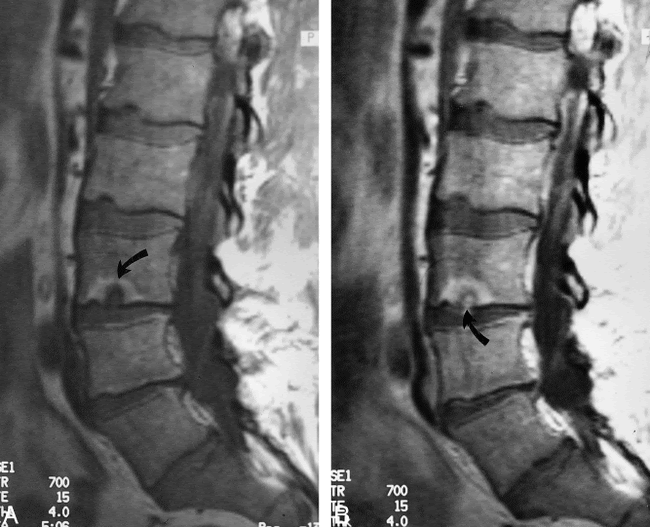

Sagittal Mr Images Of A Lumbar Spine With Classic Schmorl Nodes A Download Scientific Diagram